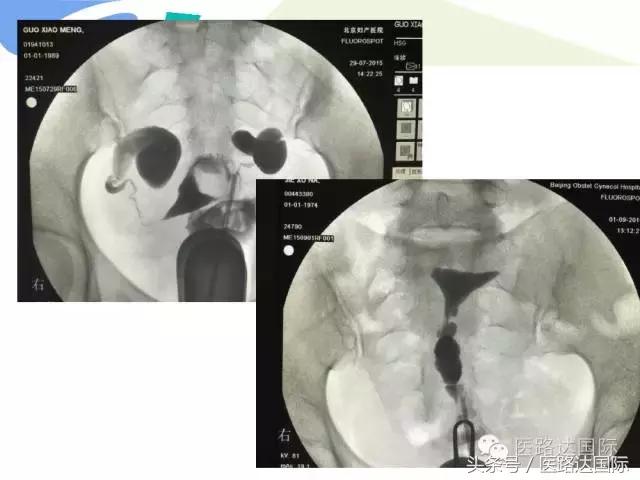

首都医科大学附属北京妇产医院梁宇霆教授从流行病学、临床特点、实验室检查、病理改变、影像学特点及治疗与预后六个方面向我们详细地介绍了女性生殖系统结核;并且着重介绍了子宫输卵管造影(HSG)的作用。在最后,梁教授还向大家介绍了如何鉴别诊断女性生殖系统结核、盆腔炎性病变和卵巢癌。